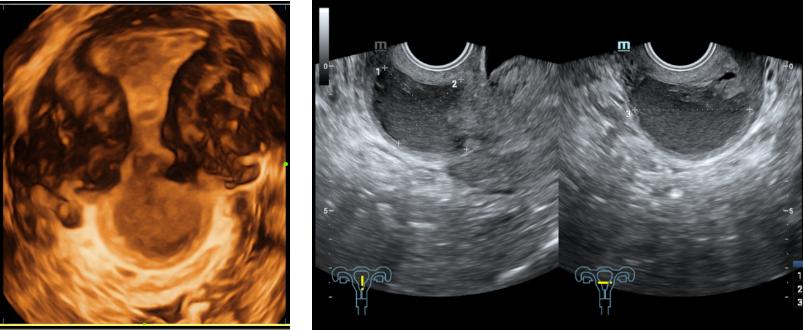

2020-03-30本院经腹子宫附件超声检查示:盆腔内探及两个子宫。左侧子宫正常大,内膜厚0.34cm(双层),宫壁回声均匀。右侧子宫正常大,内膜厚0.29cm(双层),宫壁回声均匀。阴道内见5.6*4.1*3.0cm暗区,内液稠,下端距会阴口约1.6cm.右卵巢正常大,回声无殊。左卵巢内见3.5*3.2*3.7cm囊性块,内呈絮状回声。备注:右肾正常大,回声无殊,左肾区未及明显肾脏回声。诊断结果:双子宫阴道积液(阴道斜隔综合症可能),左卵巢内囊性块(黄体囊肿可能)。

患者末次月经3月28日,处于月经期,超声示“阴道内见5.6*4.1*3.0cm暗区,内液稠,下端距会阴口约1.6cm”。遂在硬膜外麻醉下行宫腔镜阴道斜隔切断术。术中见:右下方可见右侧宫颈,略小,光滑,未见明显赘生物,宫颈口见经血流出,阴道左上侧壁可见一肌性斜隔组织,略突起,粉色,隔表面光滑,未见明显开口,左侧宫颈因斜隔阻挡不可见。操作:针状电切割器以斜隔最突出处为起始点逐步切开阴道斜隔组织,见暗红色积血流出,约30ml,陈旧性经血流出后阴道壁包块完全塌陷,宫腔镜下无法完全探及斜隔边缘,行阴道检查,可及斜隔面积约2.0*1.5cm,遂行经阴道斜隔电切术,剪刀扩大斜隔边缘,完全切除斜隔组织,切缘电凝止血,2-0可吸收线连续锁边缝合止血。术后诊断:阴道斜隔综合征I型。